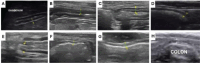

Ultrasound (USG) is a valuable diagnostic tool for evaluating the gastrointestinal tract of cats, providing noninvasive and dynamic information. B-mode USG allows evaluation of intestinal wall thickness, stratification, motility, and adjacent structures, such as lymph nodes and peritoneum. The stomach and intestinal segments can be differentiated based on their location, wall stratification, and relationships with surrounding organs. Normal ultrasound parameters, including gastric and intestinal wall thickness, peristaltic activity, and luminal content appearance, have been established for cats. Doppler ultrasound was used to assess vascular flow in the celiac and cranial mesenteric arteries and detect hemodynamic changes associated with gastrointestinal diseases. Alterations in flow velocity, resistivity index, and pulsatility index provide insights into vascular resistance and parenchymal function. Doppler velocimetry can also differentiate normal from pathological flow patterns, thereby aiding in the diagnosis of inflammatory, neoplastic, and ischemic conditions. Ultrasound findings of feline chronic enteropathy include wall thickening, loss of layering, and altered vascular supply. Lymphoplasmacytic enteritis and alimentary lymphoma, which are common in cats, present overlapping USG features, requiring histopathology for definitive diagnosis. Doppler alterations in the mesenteric arteries reflect gastrointestinal inflammation and ischemia, highlighting their potential as complementary diagnostic tools. Although B-mode and Doppler ultrasound are effective in identifying gastrointestinal abnormalities, further studies are needed to establish reference values and refine their clinical applications. The integration of these techniques enhances the noninvasive assessment of feline enteropathies and contributes to improved diagnosis and management. This review explores the use of B-mode and Doppler ultrasound for assessing the stomach and intestines in healthy and diseased felines.